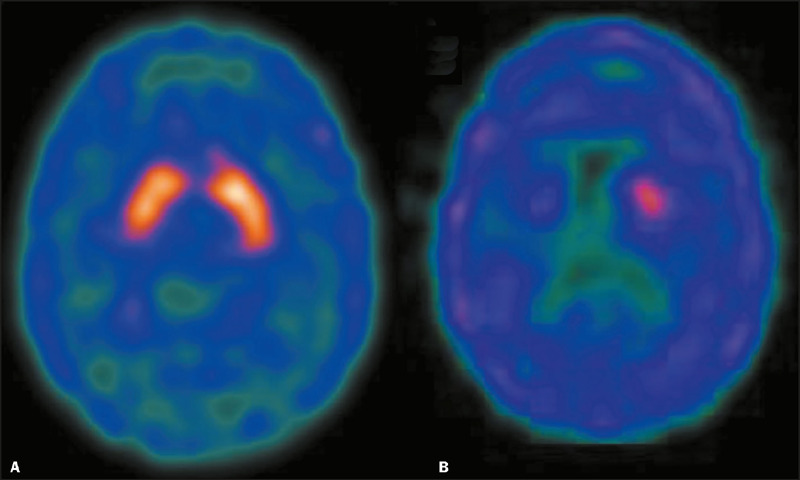

Objective: To compare the dopamine transporter (DAT) density with other risk factors for L-DOPA-induced dyskinesia (LID) in patients with Parkinson's disease (PD), with and without LID.

Materials and methods: We evaluated 67 subjects: 44 patients with idiopathic PD of varying degrees of severity (PD group), and 23 healthy age-matched volunteers (control group). Among the 44 patients in the PD group, 29 were male and the following means were recorded at baseline: age, 59 ± 7 years; disease duration, 10 ± 6 years; Hoehn and Yahr (H&Y) stage, 2.16 ± 0.65; and Unified Parkinson's Disease Rating Scale part III (UPDRS III) score, 29.74 ± 17.79. All subjects underwent 99mTc-TRODAT-1 SPECT. We also calculated specific uptake ratios or binding potentials in the striatum.

Results: The DAT density in the ipsilateral and contralateral striata was lower in the PD group. The variables disease duration, L-DOPA dosage, doses per day, L-DOPA effect duration time, H&Y stage, and UPDRS III score explained the occurrence of LID. The DAT density in the ipsilateral striatum, contralateral striatum, and caudate nucleus was lower in the patients with LID than in those without.

Conclusion: Our findings suggest that presynaptic dopaminergic denervation is associated with LID in individuals with PD.